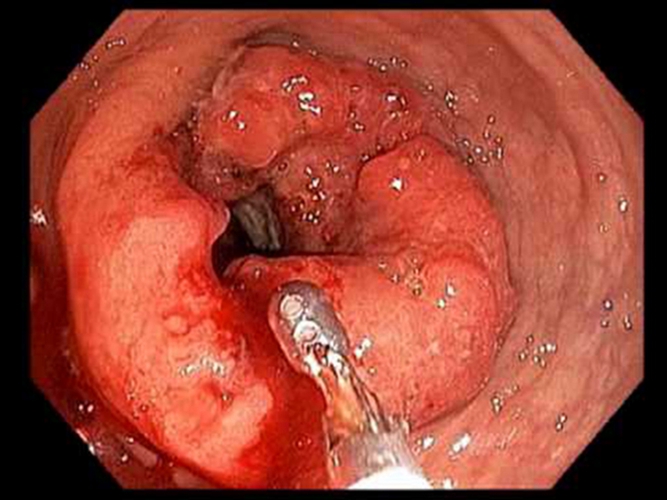

右半結腸癌腺癌

右半結腸癌腺癌一級

右半結腸癌圓形未分化癌常見 臨床 特點

右半結腸癌粘液腺癌常見 臨床特點

右半結腸癌腺癌浸潤型常見臨床特點

右半結腸癌腺癌三級常見臨床 特點

右半結腸癌腺癌二級常見臨床 特點

右半結腸癌未分化癌常見臨床特點

右半結腸癌潰瘍型常見臨床 特點

右半結腸癌的粘液腺癌常見臨床特點

右半結腸癌浸潤型常見臨床 特點

右半結腸癌的腺癌常見 臨床 特點

右半結腸癌的腺癌二級常見 臨床特點

右半結腸癌的腺癌一級常見 臨床特點

右半結腸癌不規則形未分化癌常見 臨床 特點

右半結腸癌的未分化癌常見臨床 特點

乙狀結腸癌潰瘍型症狀

乙狀結腸癌未分化癌早期 症狀